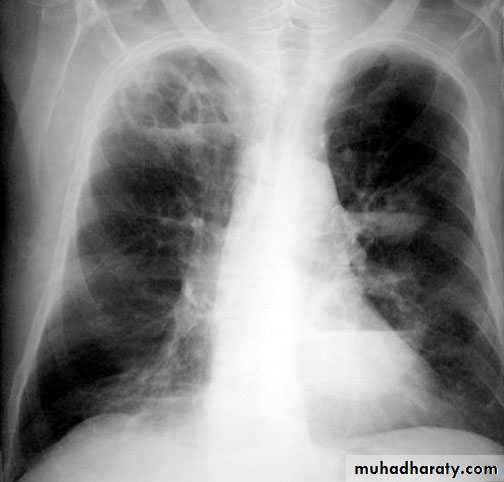

Post primary tb

TB lung